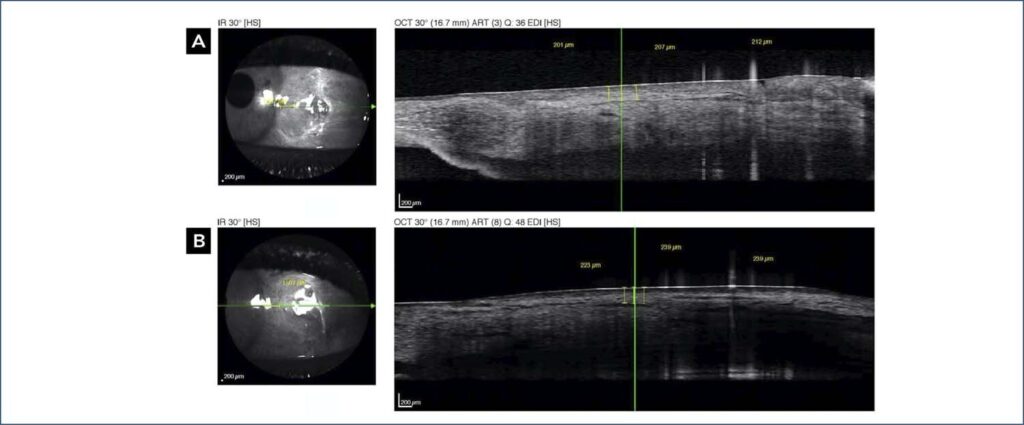

Neste ensaio clínico randomizado, 30 olhos de 30 pacientes submetidos à cirurgia de pterígio foram divididos em um Grupo de Técnica de Dissecção de Moscovici e um Grupo de Dissecção Manual. Os pacientes foram tratados e avaliados no Hospital Oftalmológico Visão Laser (Santos, São Paulo, Brasil). A tomografia de coerência óptica foi realizada para medir a espessura do enxerto 3 meses após a cirurgia. Três imagens foram obtidas de cada olho, e três medidas foram realizadas a uma distância de 1,5mm perpendicular ao limbo em cada captura. O cirurgião classificou a dificuldade de obtenção do enxerto com a técnica realizada de um (menor dificuldade) para quatro (maior dificuldade).

Encontramos diferenças estatisticamente significantes entre a dificuldade das duas técnicas e a espessura média do autoenxerto conjuntival nos dois grupos (p=0,01 e p=0,05, respectivamente). A classificação média de dificuldade para o Grupo de Técnica de Dissecção de Moscovici foi de 1,47, enquanto a do Grupo de Dissecção Manual foi de 2,20. A espessura média das três medidas foi de 252μ no Grupo de Técnica de Dissecção de Moscovici e de 298μ no Grupo de Dissecção Manual, com medianas de 250μ e 278μ, respectivamente.